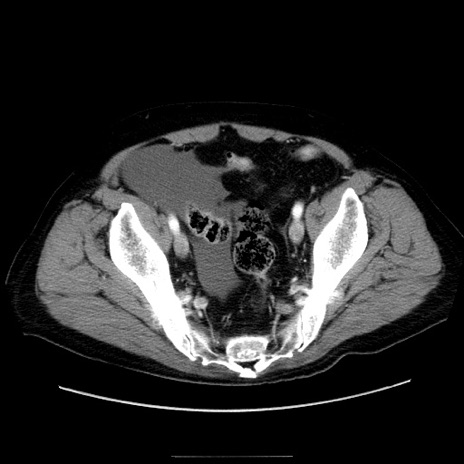

症例30(横断像)

【症例】80歳代男性

【主訴】臍周囲痛

【現病歴】約6時間前から臍下部痛が出現。次第に腹部膨隆・背部痛も生じてきたため来院。背部痛の場所は変化しない。

【既往歴】腎盂腎炎

【身体所見】意識清明、BT 36.3℃、BP  131/87mmHg、P 87bpm、SpO2 100%(RA)、臍周囲自発痛・圧痛あり、反跳痛なし、自発痛部位に一致して板状硬あり、腹部膨隆、腸雑音減弱、CVA tenderness両側陰性。

【データ】WBC 19600、CRP 0.33